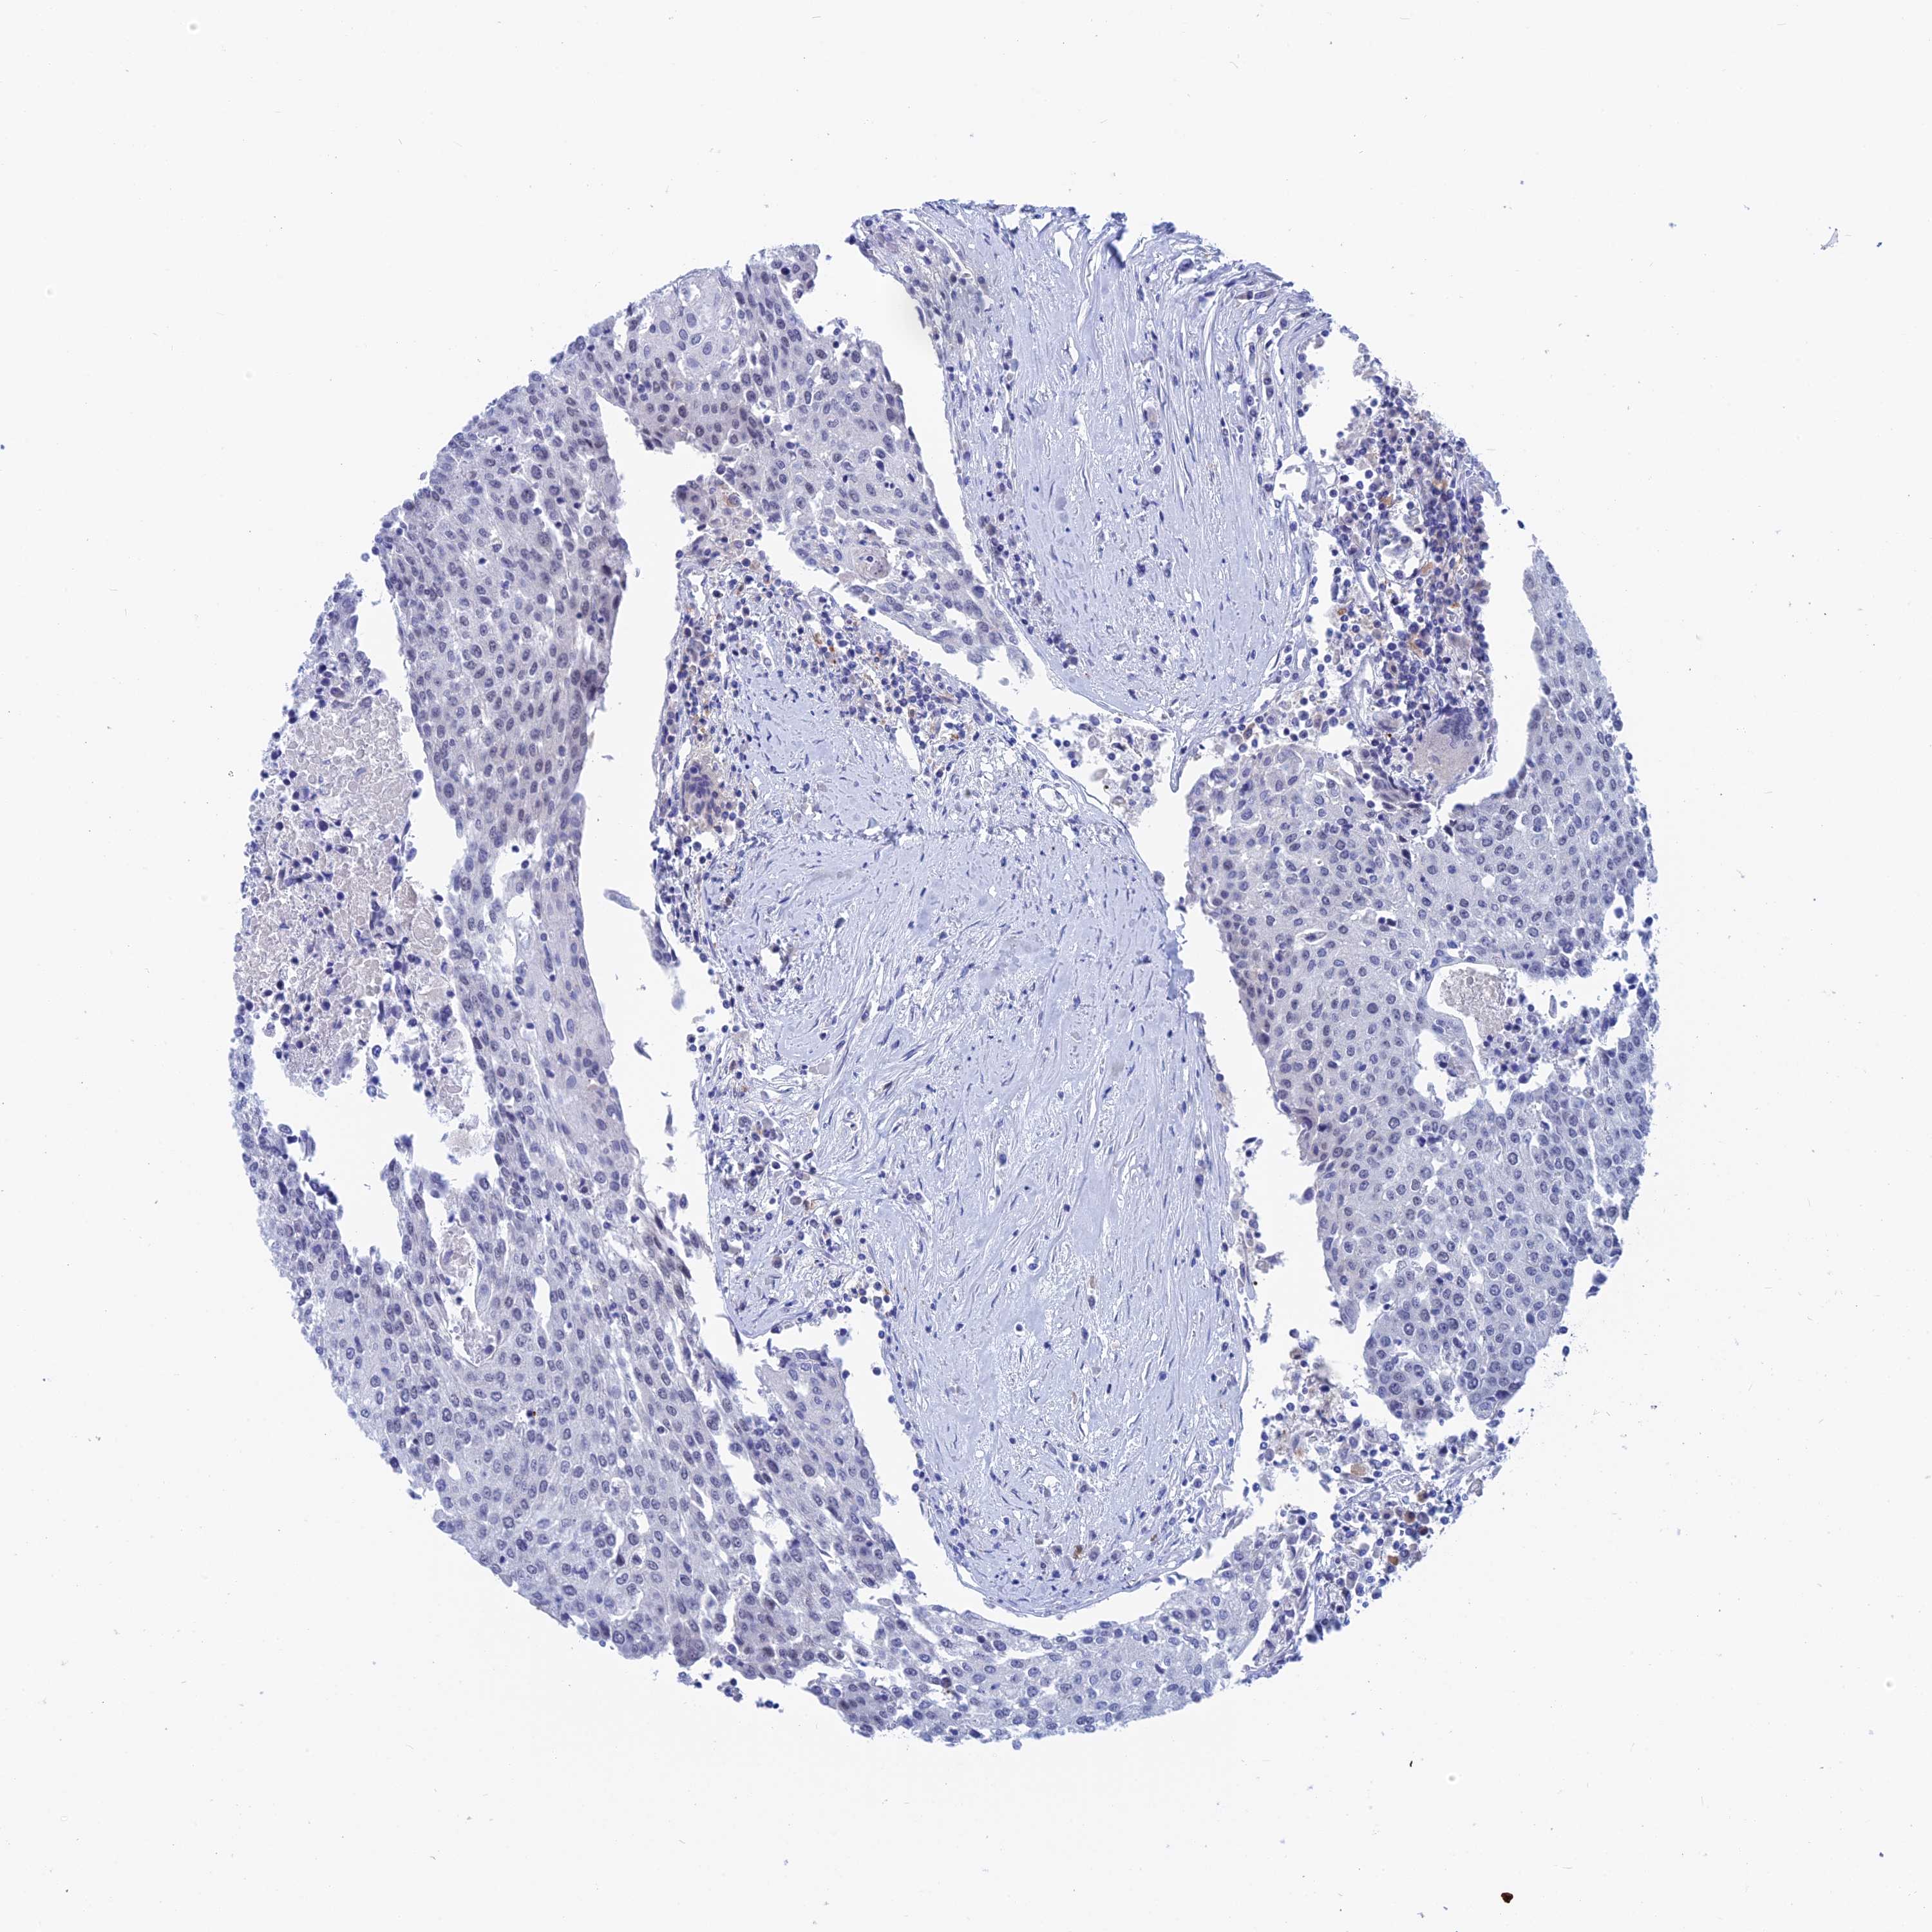

UROTHELIAL CANCER - Protein expressioni

A mouse-over function shows sample information and annotation data. Click on an image to view it in a full screen mode. Samples can be filtered based on level of antibody staining by selecting one or several of the following categories: high, medium, low and not detected. The assay and annotation is described here.

Antibody stainingi

Antibody staining in the annotated cell types in the current human tissue is reported as not detected, low, medium, or high, based on conventional immunohistochemistry profiling in selected tissues. This score is based on the combination of the staining intensity and fraction of stained cells.

Each image is clickable and will lead to virtual microscopy that enables deeper exploration of all samples and also displays staining intensity scores, fraction scores and subcellular localization as well as patient and tissue information for each sample.

Antibody HPA042629

Antibody HPA042838

Urothelial carcinoma, High grade

Urothelial carcinoma, Low grade